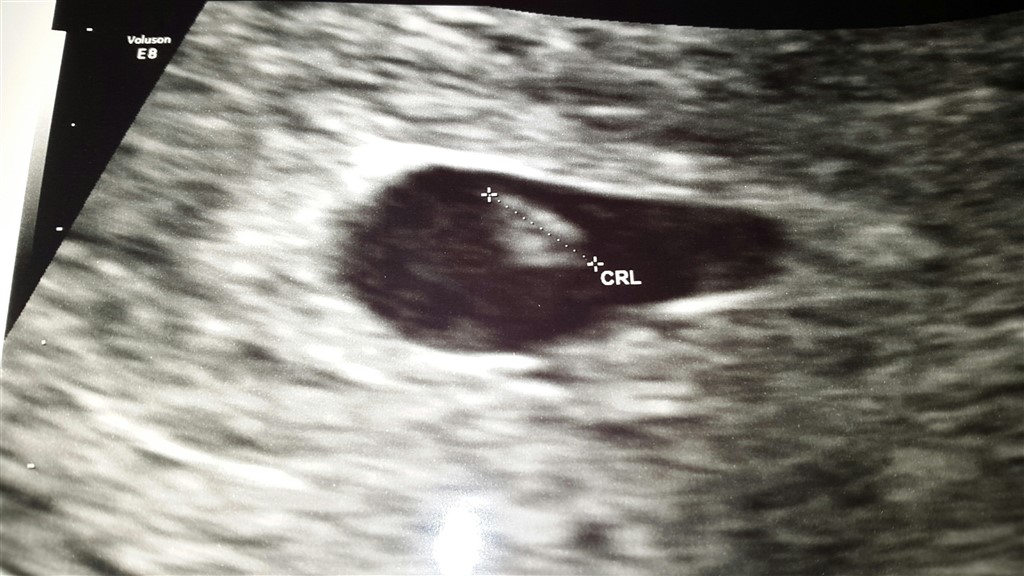

Vi bestiller en tryghedsscanning til igår, hvor jeg ifølge sidste mens burde være 9+0 ifølge mens, 7+3 ifølge clear blue digital.

Igår til scanningen vurdere hun mig så kun til at være 6+4 henne. Hvilket jeg overhovedet ikke kan få til at passe, da ægget jo kun skal have sat sig fast d. 8/11 - hvor jeg jo testede positiv første gang.

Hun mener enten, at graviditeten er gået til eller at det er en slow starter. Bortset fra dens størrelse, så så alt rigtig fint ud.

Scanningsbilledet er fra igår.